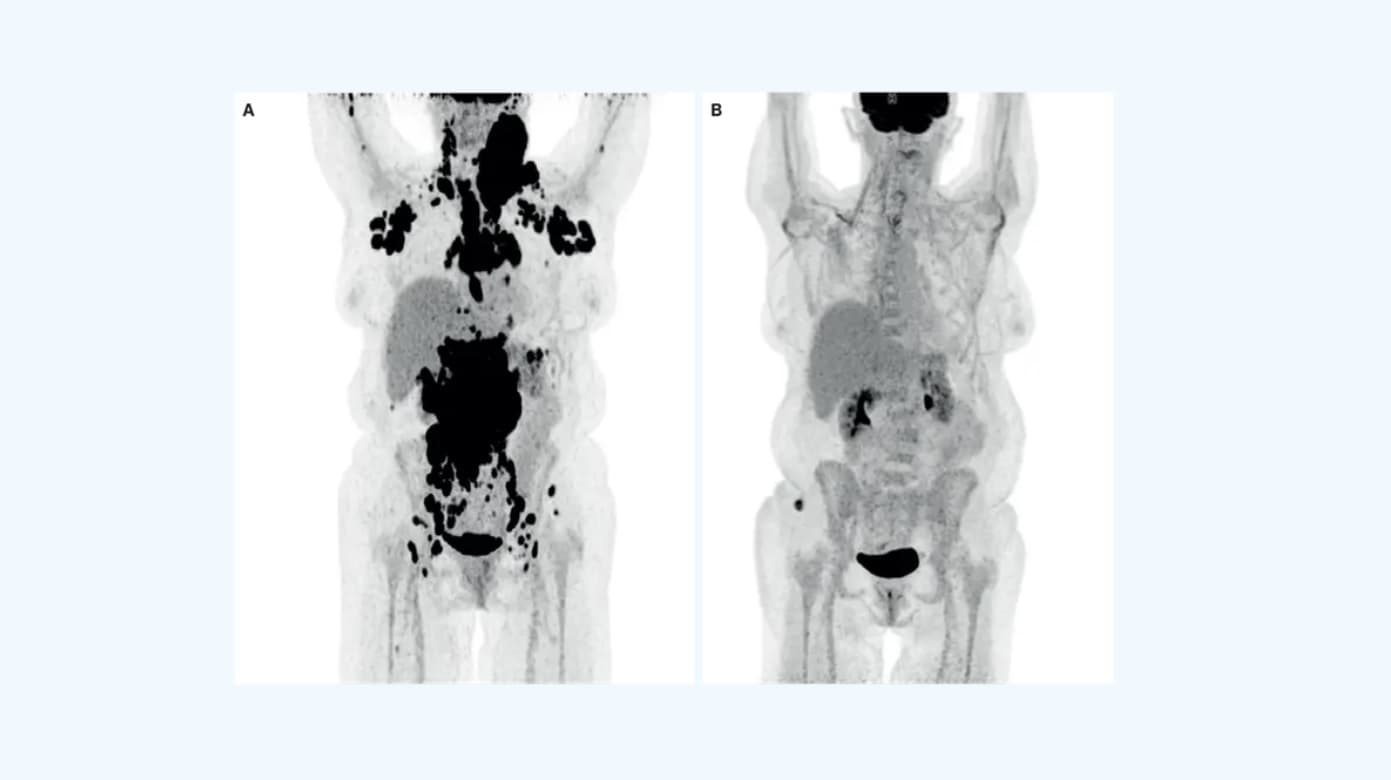

Figur 2 viser et eksempel på en ældre patient med udbredt, diffust, storcellet B-cellelymfom før og efter behandling med TCE. Patienten udviklede dag et – allerede to og en halv time efter behandling med startdosis glofitamab (TCE) – feber og takykardi og blev givet første dosis tocilizumab. I dette døgn havde patienten fortsat feber og hypotension på trods af gentagne tocilizumab- og dexamethasonbehandlinger. Patienten blev overflyttet til intensivafdeling med CRS-grad 3 til behandling med noninvasiv ventilation, vasopressorstoffer og monitorering. Patienten stabiliseredes og kunne planmæssigt modtage intermediær dosis glofitamab på ottendedagen, som var veltolereret med beskedne bivirkninger i form af CRS-grad 1, hvilket illustrerer den øgede risiko for CRS ved de(n) først(e) dosering(er).